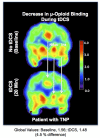

Although pain is a widely known phenomenon and an important clinical symptom that occurs in numerous diseases, its mechanisms are still barely understood. Owing to the scarce information concerning its pathophysiology, particularly what is involved in the transition from an acute state to a chronic condition, pain treatment is frequently unsatisfactory, therefore contributing to the amplification of the chronic pain burden. In fact, pain is an extremely complex experience that demands the recruitment of an intricate set of central nervous system components. This includes cortical and subcortical areas involved in interpretation of the general characteristics of noxious stimuli. It also comprises neural circuits that process the motivational-affective dimension of pain. Hence, the reward circuitry represents a vital element for pain experience and modulation. This review article focuses on the interpretation of the extensive data available connecting the major components of the reward circuitry to pain suffering, including the nucleus accumbens, ventral tegmental area, and the medial prefrontal cortex; with especial attention dedicated to the evaluation of neuroplastic changes affecting these structures found in chronic pain syndromes, such as migraine, trigeminal neuropathic pain, chronic back pain, and fibromyalgia.